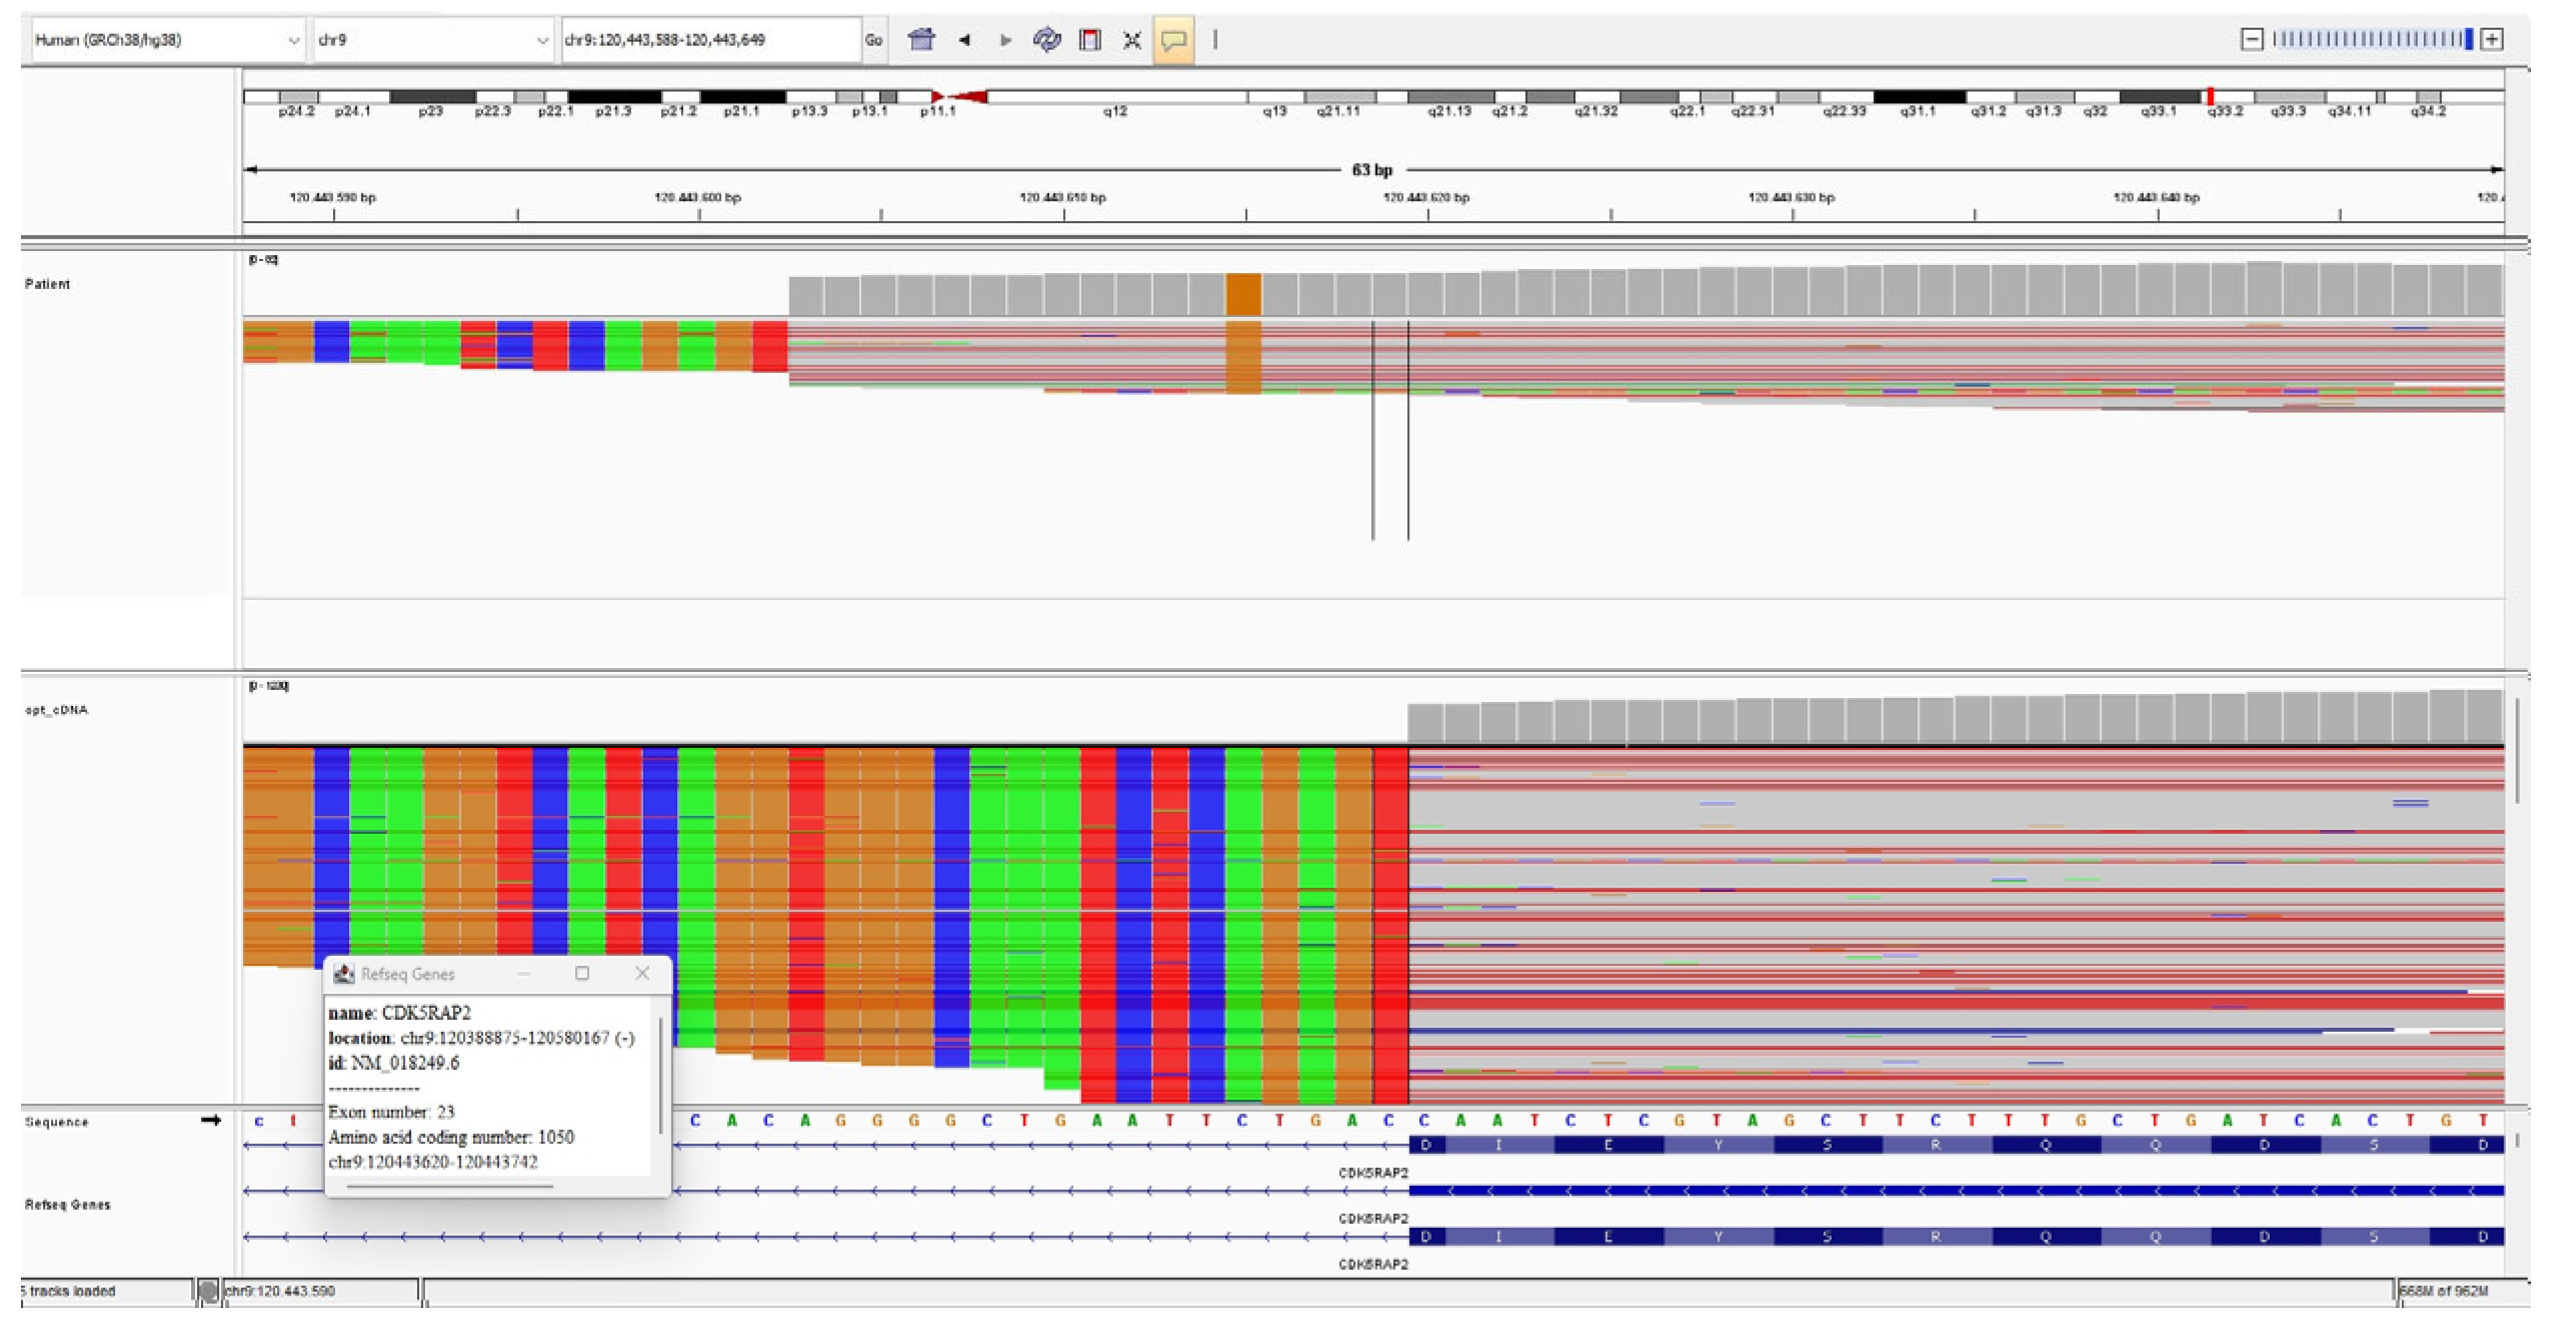

3.3. CDK5RAP2 Variants

3.4. cDNA Analysis

| CDK5RAP2 homozygous variant (NM_018249.6) | c.3148+5G>C | c.383+4dupA | c.3168del (p.Asp1057Metfs*17) | c.3168del (p.Asp1057Metfs*17) | c.1591C>T (p.Gln531*) | c.1591C>T (p.Gln531*) | c.1296dup (p.Asp433Argfs*6) |

| Variant type | Intronic | Intronic | Frameshift | Frameshift | Nonsense | Nonsense | Frameshift |